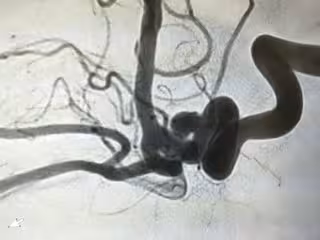

La hemorragia subaracnoidea aneurismática, una patología grave ocasionada por la rotura de un aneurisma cerebral (pequeña dilatación en forma de saco de las arterias del cerebro), es una variedad del ictus que representa el 5 por ciento de los mismos pero el 25 por ciento de la mortalidad.

Este problema, según el experto, ha de tratarse con la mayor de las urgencias una vez se presenta. "El aneurisma debe ser excluido definitivamente de la circulación cerebral, bien por embolización a través de un cateterismo, bien por clipaje de su cuello mediante operación quirúrgica", explica Gilo.

En algunas ocasiones, los aneurismas cerebrales sufren pequeñas roturas que se manifiestan en el individuo en forma de súbitos e intensos dolores de cabeza. Según este neurólogo, "la realización de pruebas de imagen de la circulación cerebral, a través de resonancia magnética o TC, puede detectarlos y, de este modo, permitir que se actúe actuar sobre ellos antes de que provoquen una hemorragia cerebral más grave".